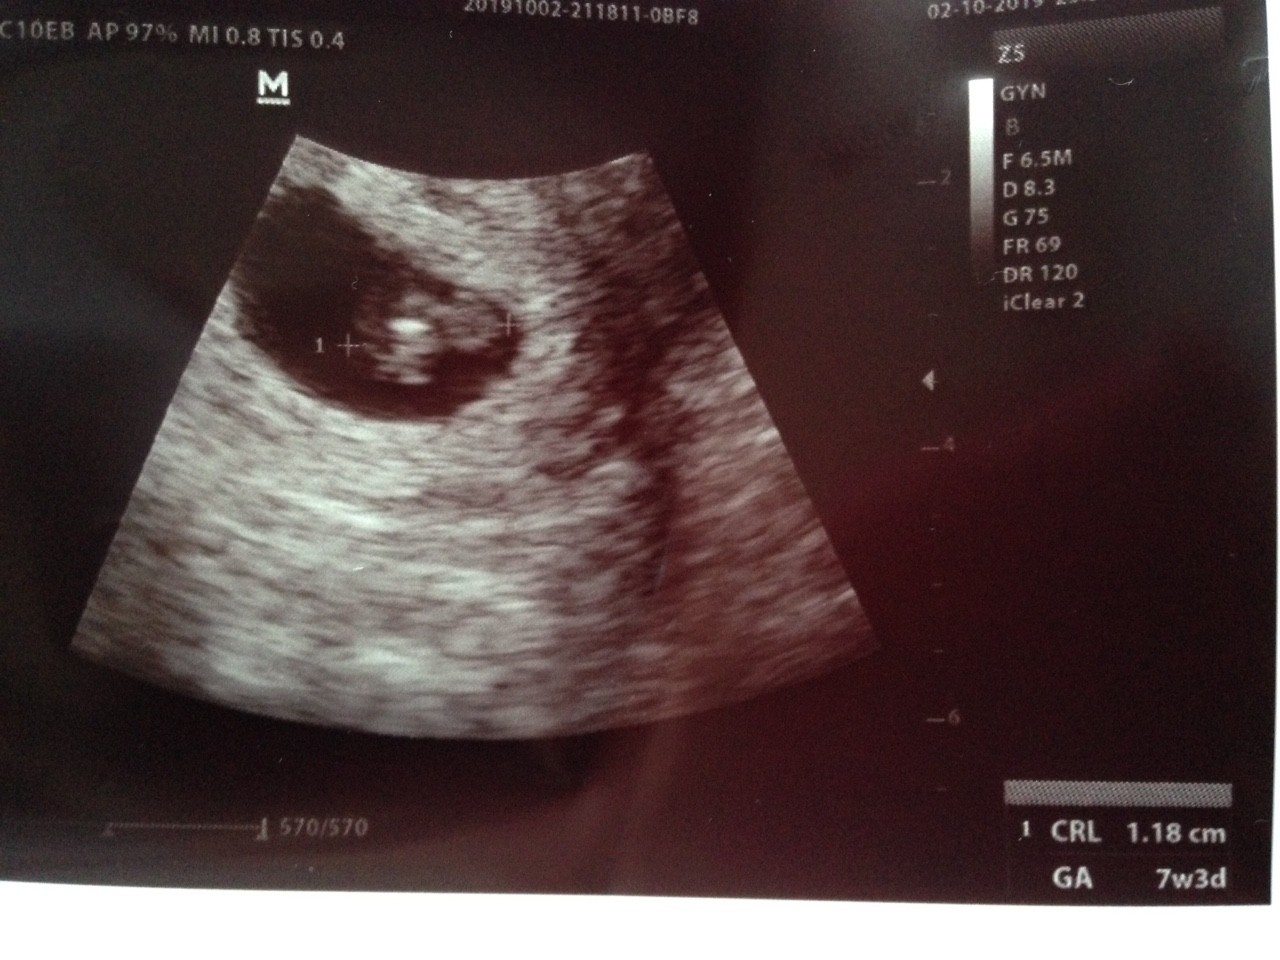

To ja też tutaj dołączę zdjęcia z ostatnich wizyt. Te zdjęcia sprawiły mi największą radość podczas tej ciąży.

Zobacz załącznik 1031911